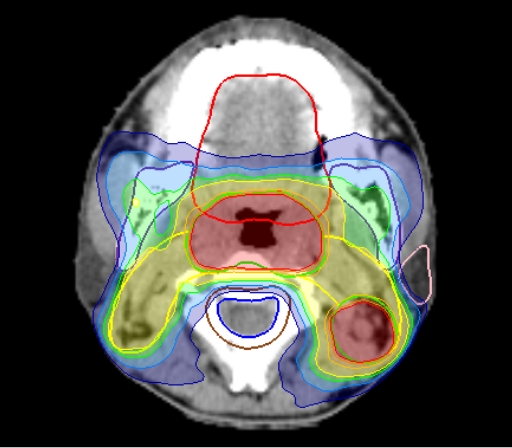

がんの部分に十分な放射線を照射して効果を高めるとともに、周囲の正常組織にはなるべく放射線を当てないようにして副作用を減らすことが重要です。そのため、無駄なく放射線を集中させる「高度な技術」が大切です。

高精度放射線治療とは、腫瘍に集中した照射を行うことで治療成績の向上や副作用低減を目的とした治療技術です。当院で行っている治療技術を紹介します。

ターゲット(腫瘍)の形状が不整形で複雑な場合やリスク臓器が隣接している場合、従来の放射線照射法では腫瘍周囲の正常組織や臓器にも腫瘍と同じ線量が照射されてしまい、腫瘍制御率(腫瘍の広がりや大きくなることを抑えられた割合)を高率に維持しながら合併症を低く抑えることが困難でした。IMRTは、腫瘍に放射線を集中して照射できる革新的な照射技術です。これにより合併症を低く抑えながら根治性を高めるといった従来では実現不可能であった放射線治療が可能になりました。 - SRT(定位放射線治療)

ターゲットに対して放射線をピンポイントで照射することにより、線量を集中させて治療を行う方法です。一度に高線量の放射線をがんの部分に照射することができるため、治療は数回で終了します。これにより、正常組織への影響を低減しながら、がんの部分をしっかり治療することが可能になりました。放射線をピンポイントで照射するために、治療部位の位置合わせをより精密に行う必要があります。治療中は体全体を極力動かないように固定するなどの対策を講じることで、より正確な照射が可能となります。 - IGRT(画像誘導放射線治療)

毎日の治療では、治療計画時の体位(腕の上げ方や体の向き)を再現するために、体表面に書かれた印を使用して体位を調整しています。しかし、治療するがんの部分は体の外部から正確な位置を確認することが困難です。そのため、照射の直前や照射中に得られるX線画像・CT画像を参考に寝台の位置をmm単位で動かして正確な位置合わせを行います。この技術を画像誘導放射線治療(Image-guided radiotherapy:IGRT)と言います。治療計画時には、目的の腫瘍から放射線が外れないように、腫瘍の大きさよりも少し大きめ(余白・マージン)に放射線を当てるように設定します。正確な位置合わせをすることで、このマージンをより小さくし、周囲の正常組織に対する影響を減らすことができます。